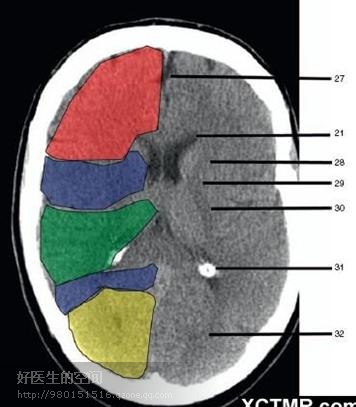

27、纵裂 (Interhemispheric fissure) 28、内囊前肢 (Anterior limb of internal capsule) 29、内囊膝部 (Genu of internal capsule) 30、内囊后肢(Posterior limb of internal capsule) 31、侧脑室三角区及脉络丛钙化(Trigone of lateral ventricle and calcified choroid plexus) 32、侧脑室枕角(Occipital horn of lateral ventricle) 绿色部分为颞叶(Temporal Lobe),浅红色部分为额叶(Frontal Lobe),黄色部分为枕叶(Occipital Lobe),褐色部分为顶叶(Parietal Lobe)